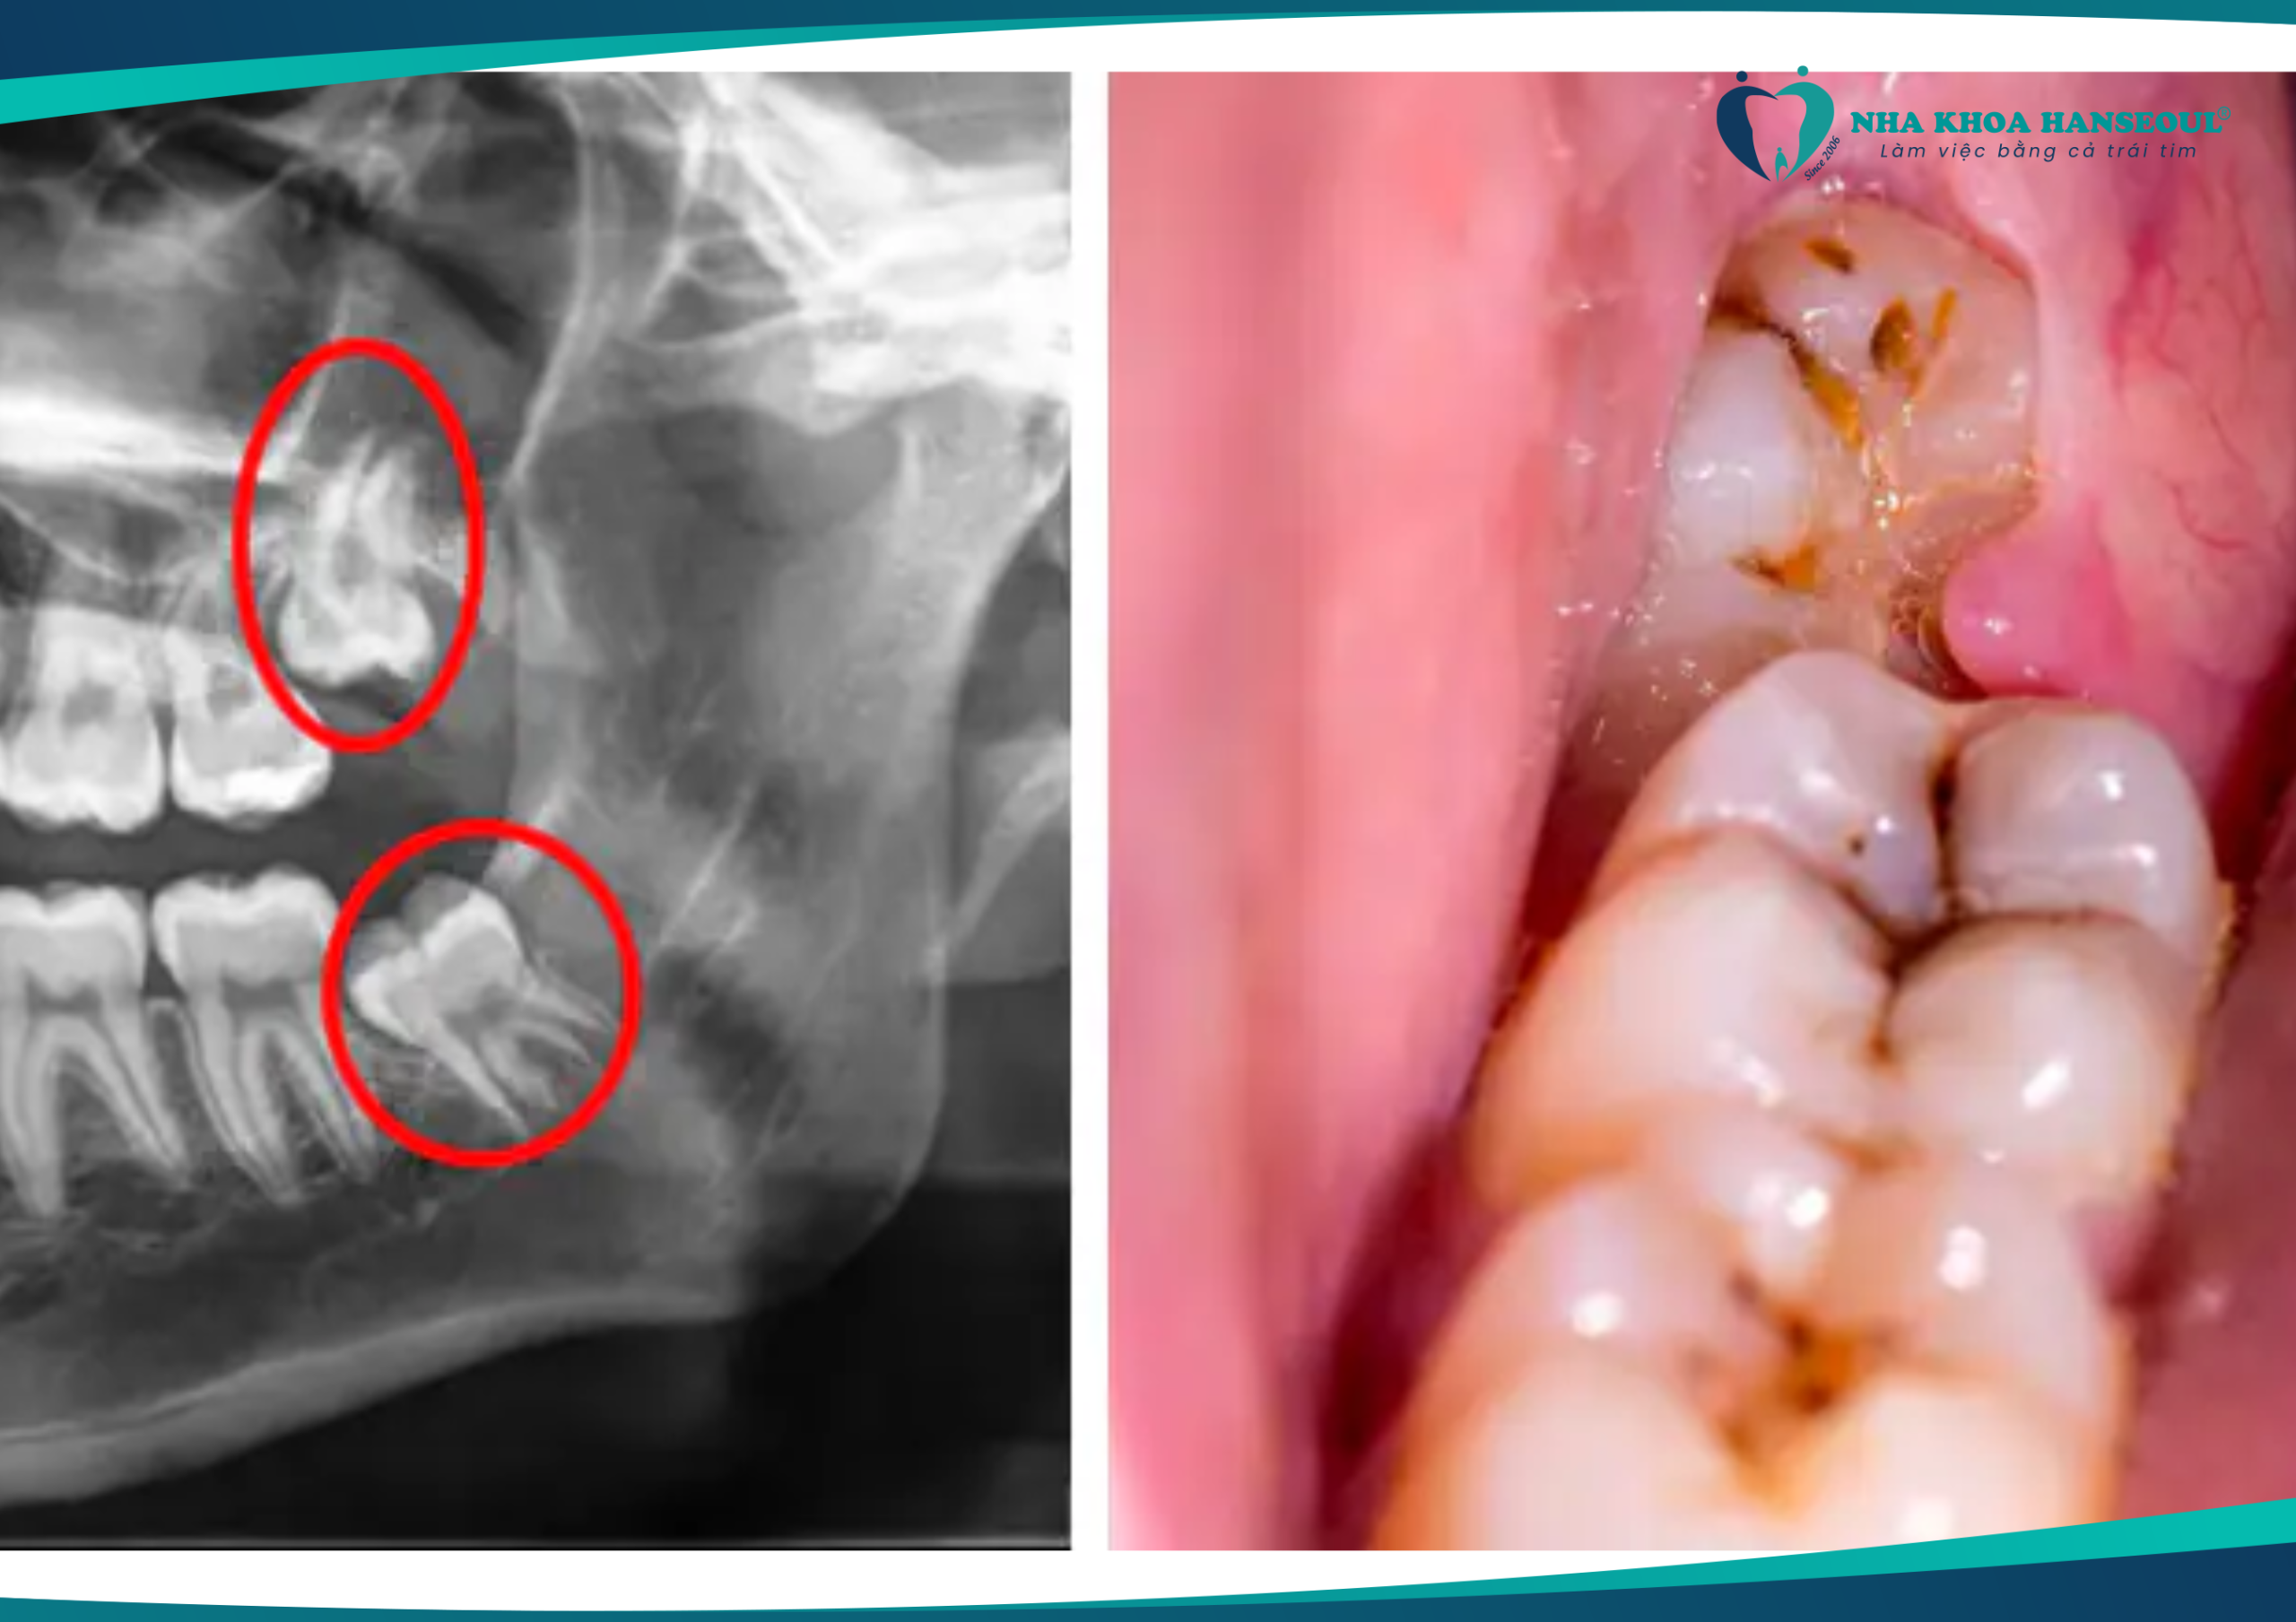

Có nên nhổ răng số 8 khi đang niềng răng?